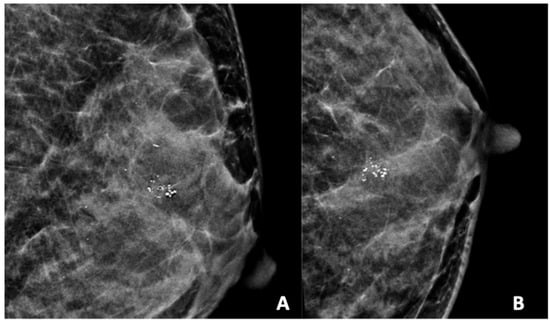

Figure 2, Figure 3, Figure 4, Figure 5 and Figure 6 show examples of the different microcalcification morphologies and distributions, while Figure 6 shows an example of a mammographic mass and an image of a complementary ultrasound assessment of the mass.

Figure 2.

Mammogram study of a left breast in (A) mediolateral (MLO) view and (B) craniocaudal (CC) view, showing amorphous calcifications in a segmental distribution in the upper outer quadrant, reported as a BI-RADS 4 lesion. Given these calcifications, a stereotactic-guided core biopsy was performed; the HPE showed DCIS. There were also benign coarse calcifications in the upper outer and mid-inner quadrants.